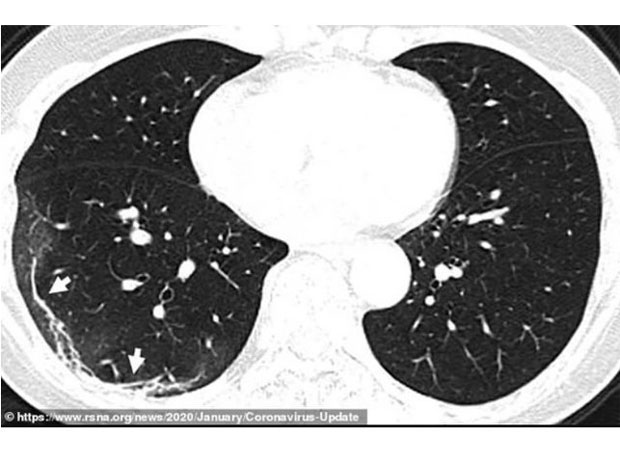

Na snimcima se vide bijele, razgranate sjenke u donjim uglovima pluća, što ukazuje na ono nešto što radiolozi zovu “neprovidno staklo” – djelimično ispunjene vazdušne prostore. Takve abnormalnosti slične su onima pronađenim kod pacijenata koji su imali SARS ili MERS, piše “Dejli mejl”.

Snimci CT skenera 54-godišnje žene koja je dobila virus nakon putovanja u Vuhan pokazuju delimično ispunjene vazdušne prostore. Ženi je dijagnostikovana teška upala pluća uzrokovana virusom, a imala je simptome kašlja, groznice, umora i kongestije grudnog koša. Ljekari su joj davali kiseonik i antibiotike.